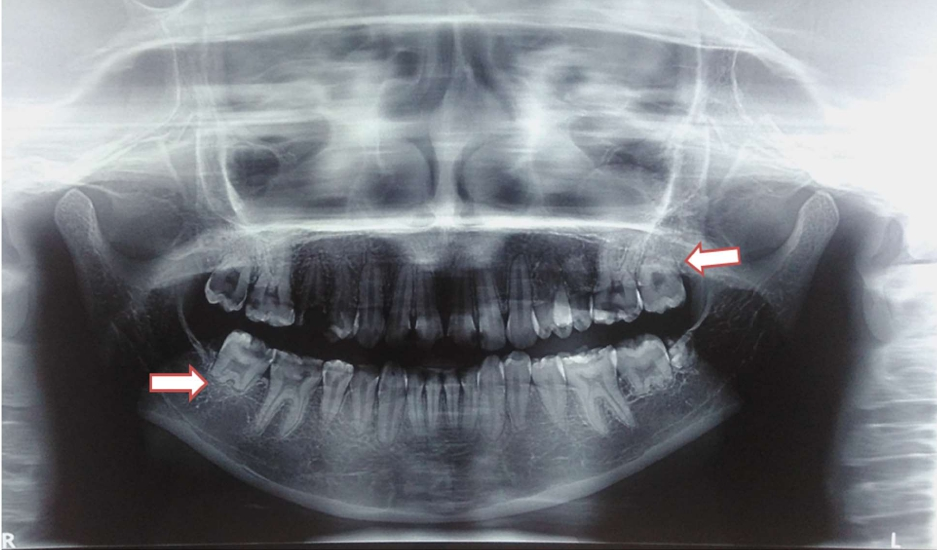

Patient received External Beam Radiation Therapy (EBRT) ten years ago. EBRT detail was 41.4 Gray/23 fractions/32 days to bilateral face and neck by bilateral portals using Cobalt 60 gamma radiation at the rate of 180 centigrays per fraction followed by a dose of 10.8 Gray/6 fractions/8 days. Total dose received by the patient was 52.2 Gray/29 fractions/40 days. A Panoramic radiograph (PAN) was advised. PAN revealed radicular hypoplasia (arrow in figure) in relation to both maxillary and mandibular second molars with missing maxillary third molars bilaterally and mandibular right third molar. Also crown of mandibular left third molar was malformed. All canines and premolars were present with stunted roots. Further, hypoplastic condyles were also seen (Figure 1). Diagnosis of Radiation Induced Radicular Hypoplasia (RIRH) was made in relation to both maxillary and mandibular second molars. Differential diagnoses of dentine dysplasia and dentinogenesis imperfecta were excluded because of their generalized nature along with peculiar features.

Figure 1: PAN showing radicular hypoplasia in relation to second molars (arrows), stunted roots of canine and premolars and condylar hypoplasia.